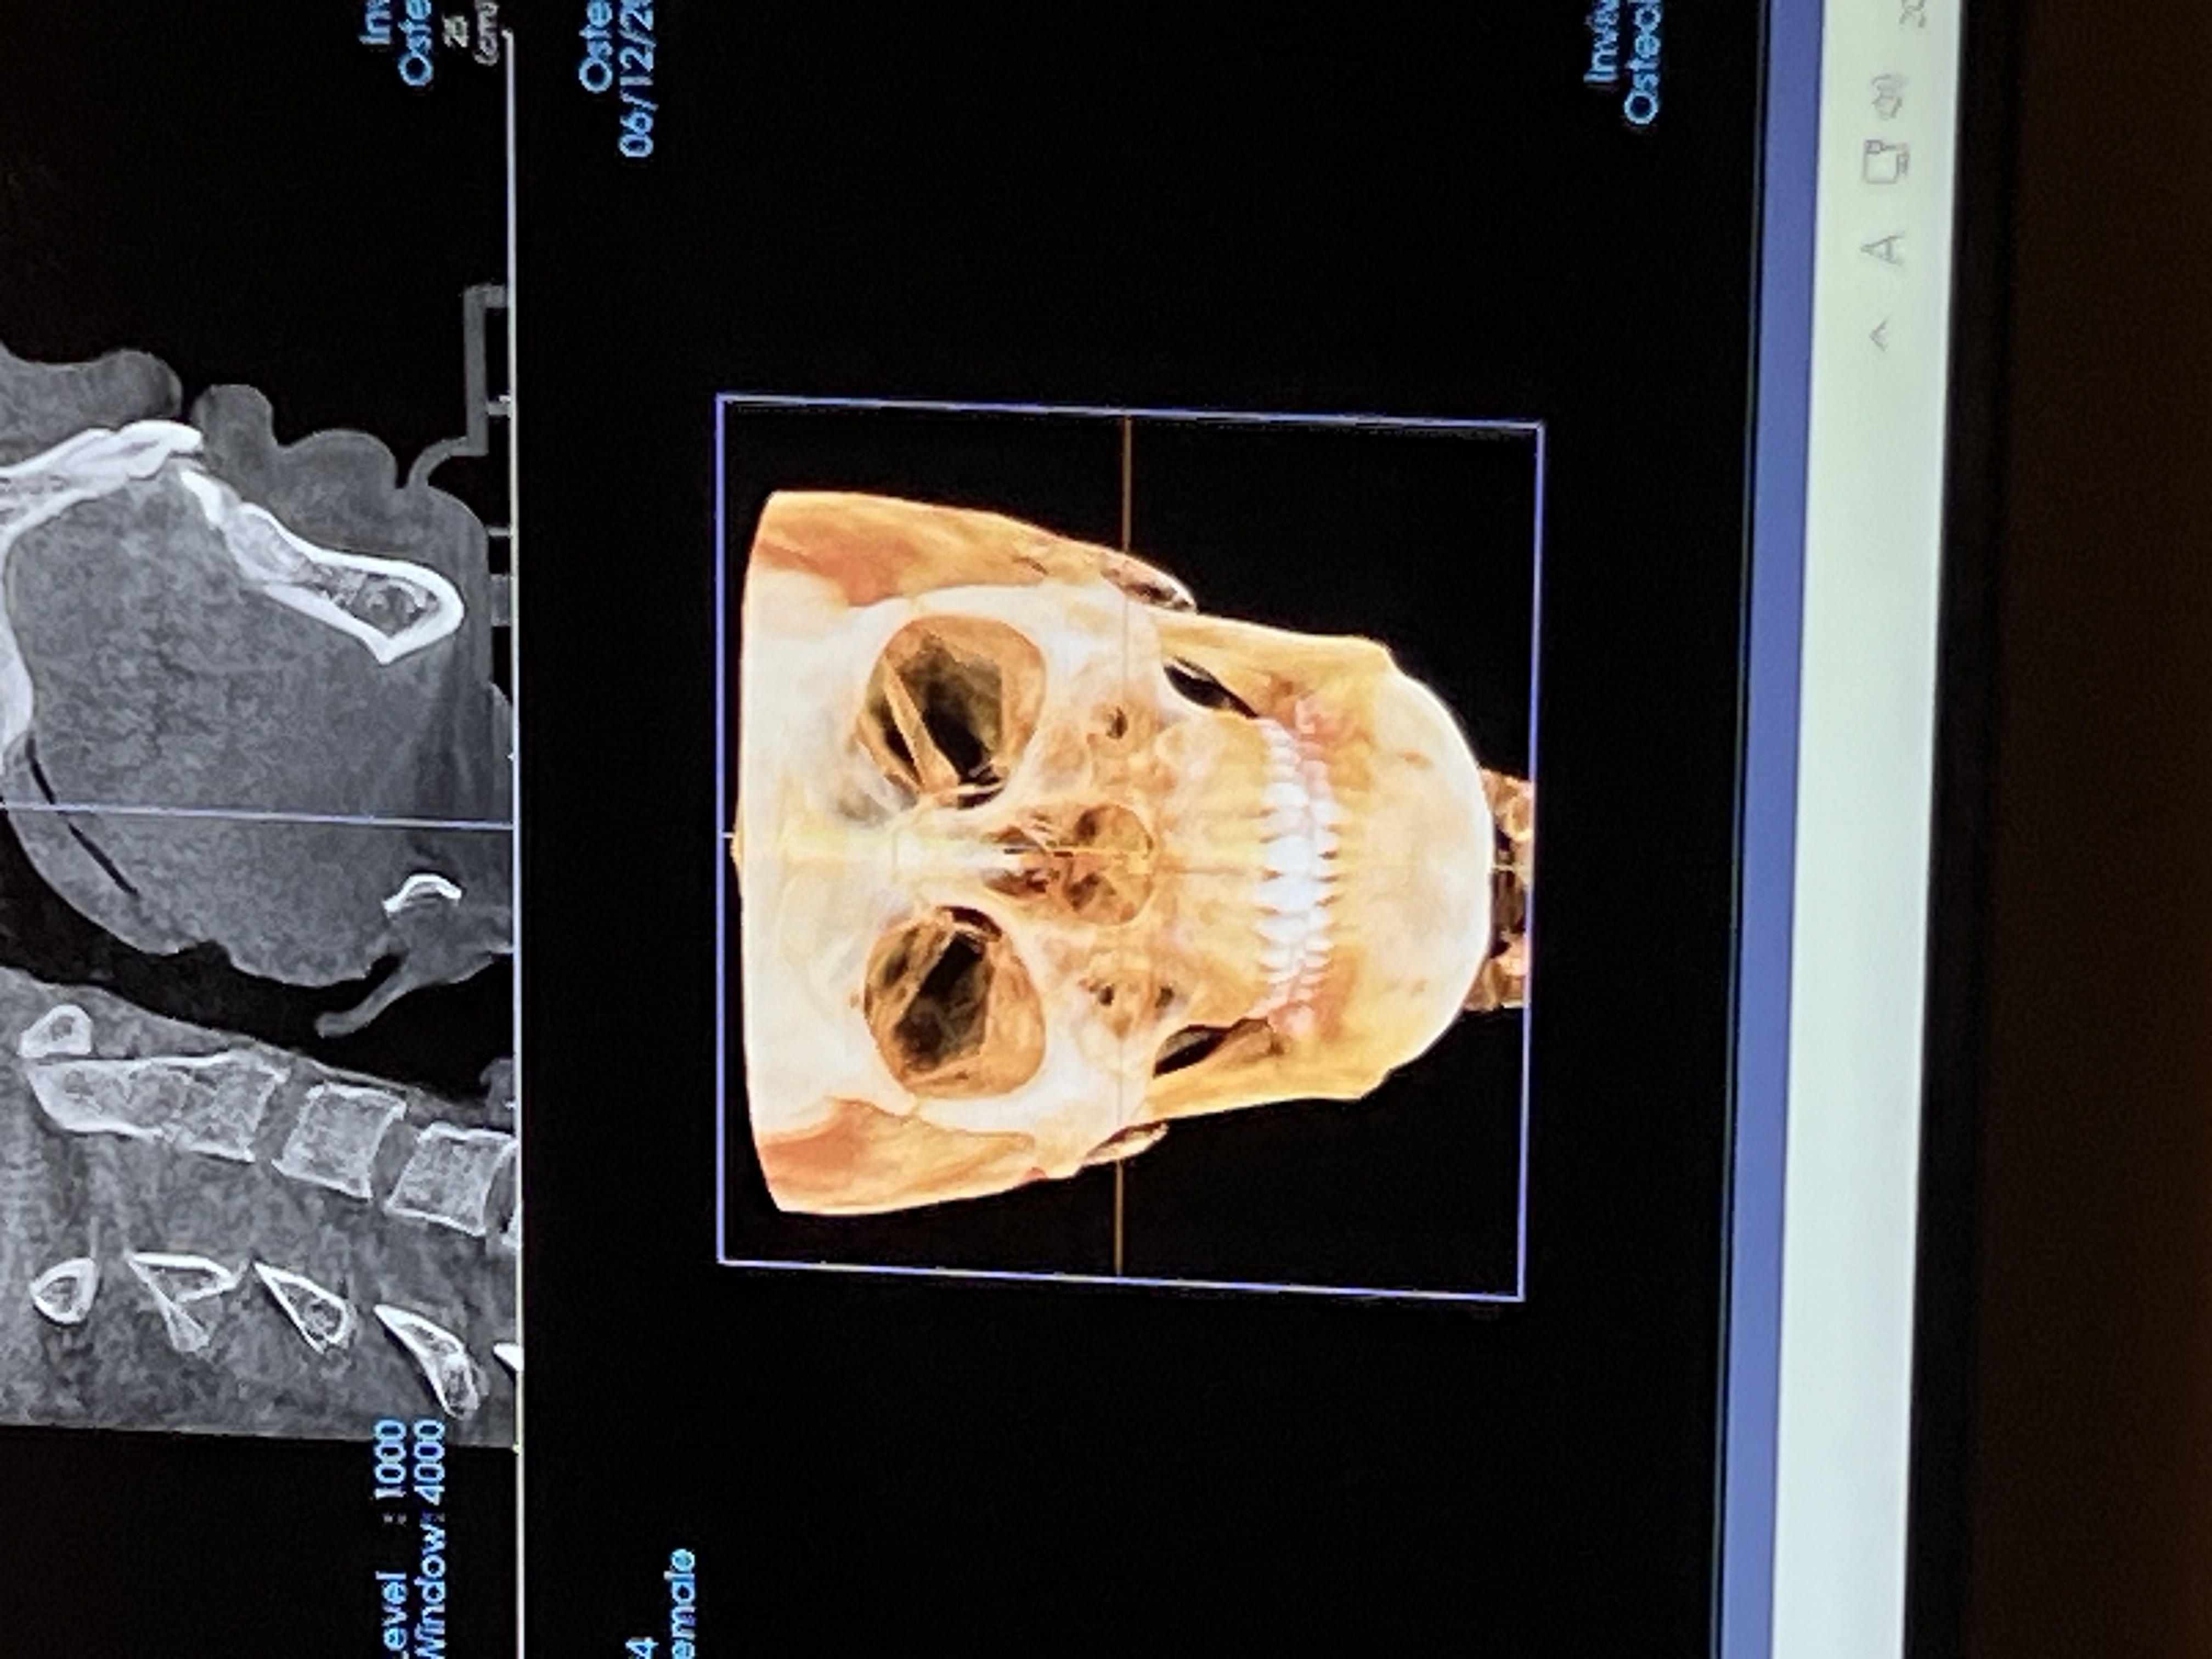

내가 신경선이 낮은편? 이거든 일단 내 제일 고민은 광대고 광대를 할건데 광대만 치면 좀 비율이 안 맞아서 턱이랑 턱이 짧아서 턱끝도 같이 하려고 해 근데 내가 고민인건 피질절골이거든 피질절골은 안하고서는 효과를 볼 수 없으려나 ?

뼈 사진만 봐서는 잘 모르겠다...

컥 나두 윤곽했엇는데 뼈사진 보니까 굳이 윤곽안하고 턱 필러만 맞아도 될듯